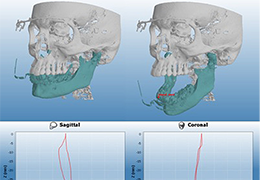

Performs 3D reconstruction and volume rendering.

Multi-planar slicing.

Oblique slicing.

Side-by-side comparative assessment for pre- and post-operative scans.